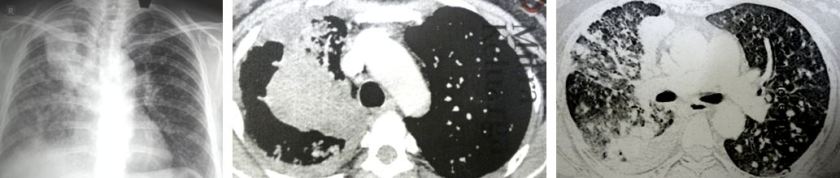

Blood tests showed her CEA was at 39.7 (high) and a CT scan showed a mass in her lung.

The doctor was monitoring her progress through X-rays. It was not until May 2018 that a CT scan was done. After seeing the scan, it was not about TB anymore. Could it be lung cancer? Or to be more precise, could it be a metastatic lung cancer?